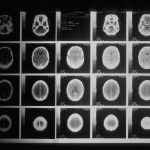

CDC/Janice Haney Carr

This 2005 scanning electron micrograph depicts clumps of methicillin-resistant Staphylococcus aureus bacteria. Magnified 9560x.